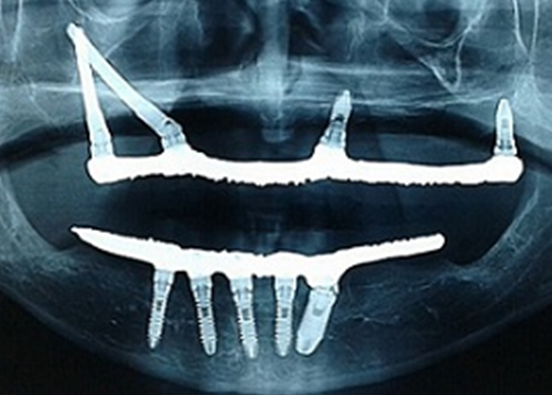

Com os dentes em posição correta e a infraestrutura passiva, foi realizada a acrilização da prótese. Findado os procedimentos laboratoriais, a prótese definitiva foi instalada três dias após o procedimento cirúrgico, onde foram realizados os primeiros ajustes oclusais necessários e orientações quanto à higienização da prótese. Nessa etapa também foi instalada e ajustada uma placa oclusal miorrelaxante, protegendo os implantes de qualquer hábito parafuncional por parte do paciente (Figura 8 -10).